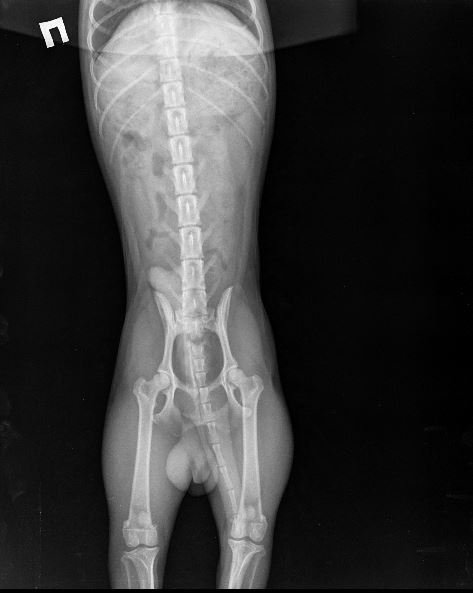

Прикладываю снимки, приблизила, чтобы лучше видно было. Также выкладываю снимок грудной клетки(этот снимок мы делали пару месяцев назад, когда он кашлял и врач исключал бронхит), на нем тоже есть ТБС, вдруг тоже на нем что-нибудь видно..

Название: 10.12.2017 Джин рентген грудной клетки (увеличение с обще.JPG

Просмотров: 674

Размер:	87.3 Кб

ID:	90395   Нажмите на изображение для увеличения

Название: 10.12.2017 Джин рентген грудной клетки 2 (увеличение с общ.JPG

Просмотров: 695

Размер:	68.6 Кб

ID:	90396

В любом случае вывиха тбс там нет. Зато отсняли во всех проекциях, вплоть до грудной клетки))) врач выполнял план по рентгену? Либо тс нам что-то не договаривает

Iriska, Наташ, в старт-посте ТС написала, что рентген ГК делали сильно раньше, просто она залила его сюда на всякий случай.